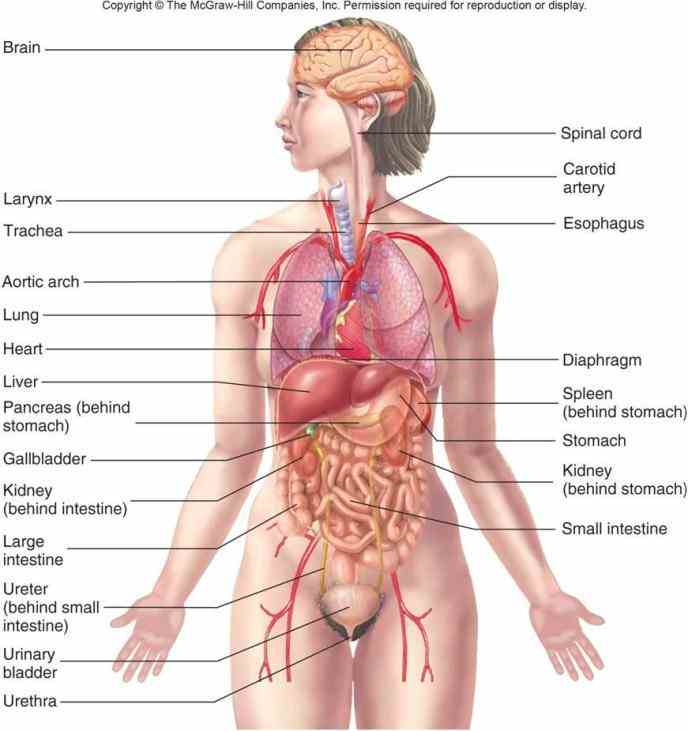

Anatomy Of Internal Organs Female – Organ Anatomy Female Anatomy …

Right Side Women’s Body Human Body Organs / Human Anatomy And …

Female Body Organs Diagram Anatomy | MedicineBTG.com

Human Anatomy Picture Organs Female Human Body Diagram Of Organs See …

Right Side Women’s Body Human Body Organs : What Do Right-Sided Organs …

Female Human Organs Diagram | MedicineBTG.com

Female Abdominal Anatomy Images . Female Abdominal Anatomy Images …

Female Abdominal Anatomy Pictures – koibana.info | Anatomy organs …

Internal Organs Adult Female Front And Back View Stock Photo – Download …

Illustration Of Female Internal Organs Photograph by Science Source

Illustration Of Female Internal Organs Photograph by Science Source

Image result for human organs diagram | Human body anatomy, Human body …

Human Female Organ Diagram . Human Female Organ Diagram Colorful Human …